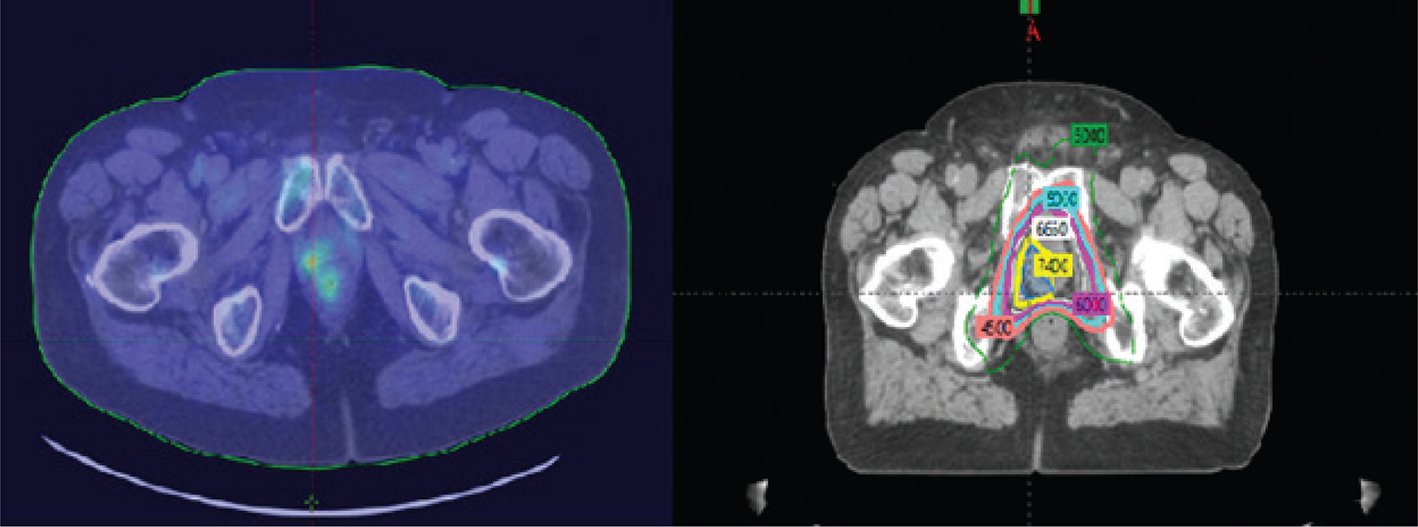

Metabolic imaging with Axumin and prostate-specific membrane antigen targeted therapy has helped define areas of disease that might otherwise be overlooked, especially in the post prostatectomy setting with elevation in PSA including identification of patients with oligometastasis (3133). Radiation oncologists can identify metabolically active areas as high-risk including sites of limited metastatic disease and treat these regions to full dose while titrating dose to metabolically inactive regions (3133). These images have altered how radiation oncologists contour nodal anatomy, and image guidance is giving confidence to the radiation oncology community to titrate target volumes. These imaging tools provide opportunity to adjust volumes to high-risk targets with dose painting and radiosurgery techniques. Optimal targeting with image guidance has the potential to improve patient outcome and decrease the immediate need for additional therapy such as hormone therapy. In the future, this effort will expand and include patients with oligometastatic disease who will be treated with definitive intent. It is anticipated we can titrate high dose volume directed to areas of metabolic and anatomical disease and place areas traditionally thought at risk and treat them to a more intermediate dose. Advanced imaging tools may provide security that we are treating the appropriate volume to the optimal dose and spare normal tissue for additional therapies to be considered at a later time point if needed (23, 24). It is becoming clear the therapy community will become more aggressive in the management of patients with advanced disease at presentation and therapies beyond traditional application of hormone therapy.